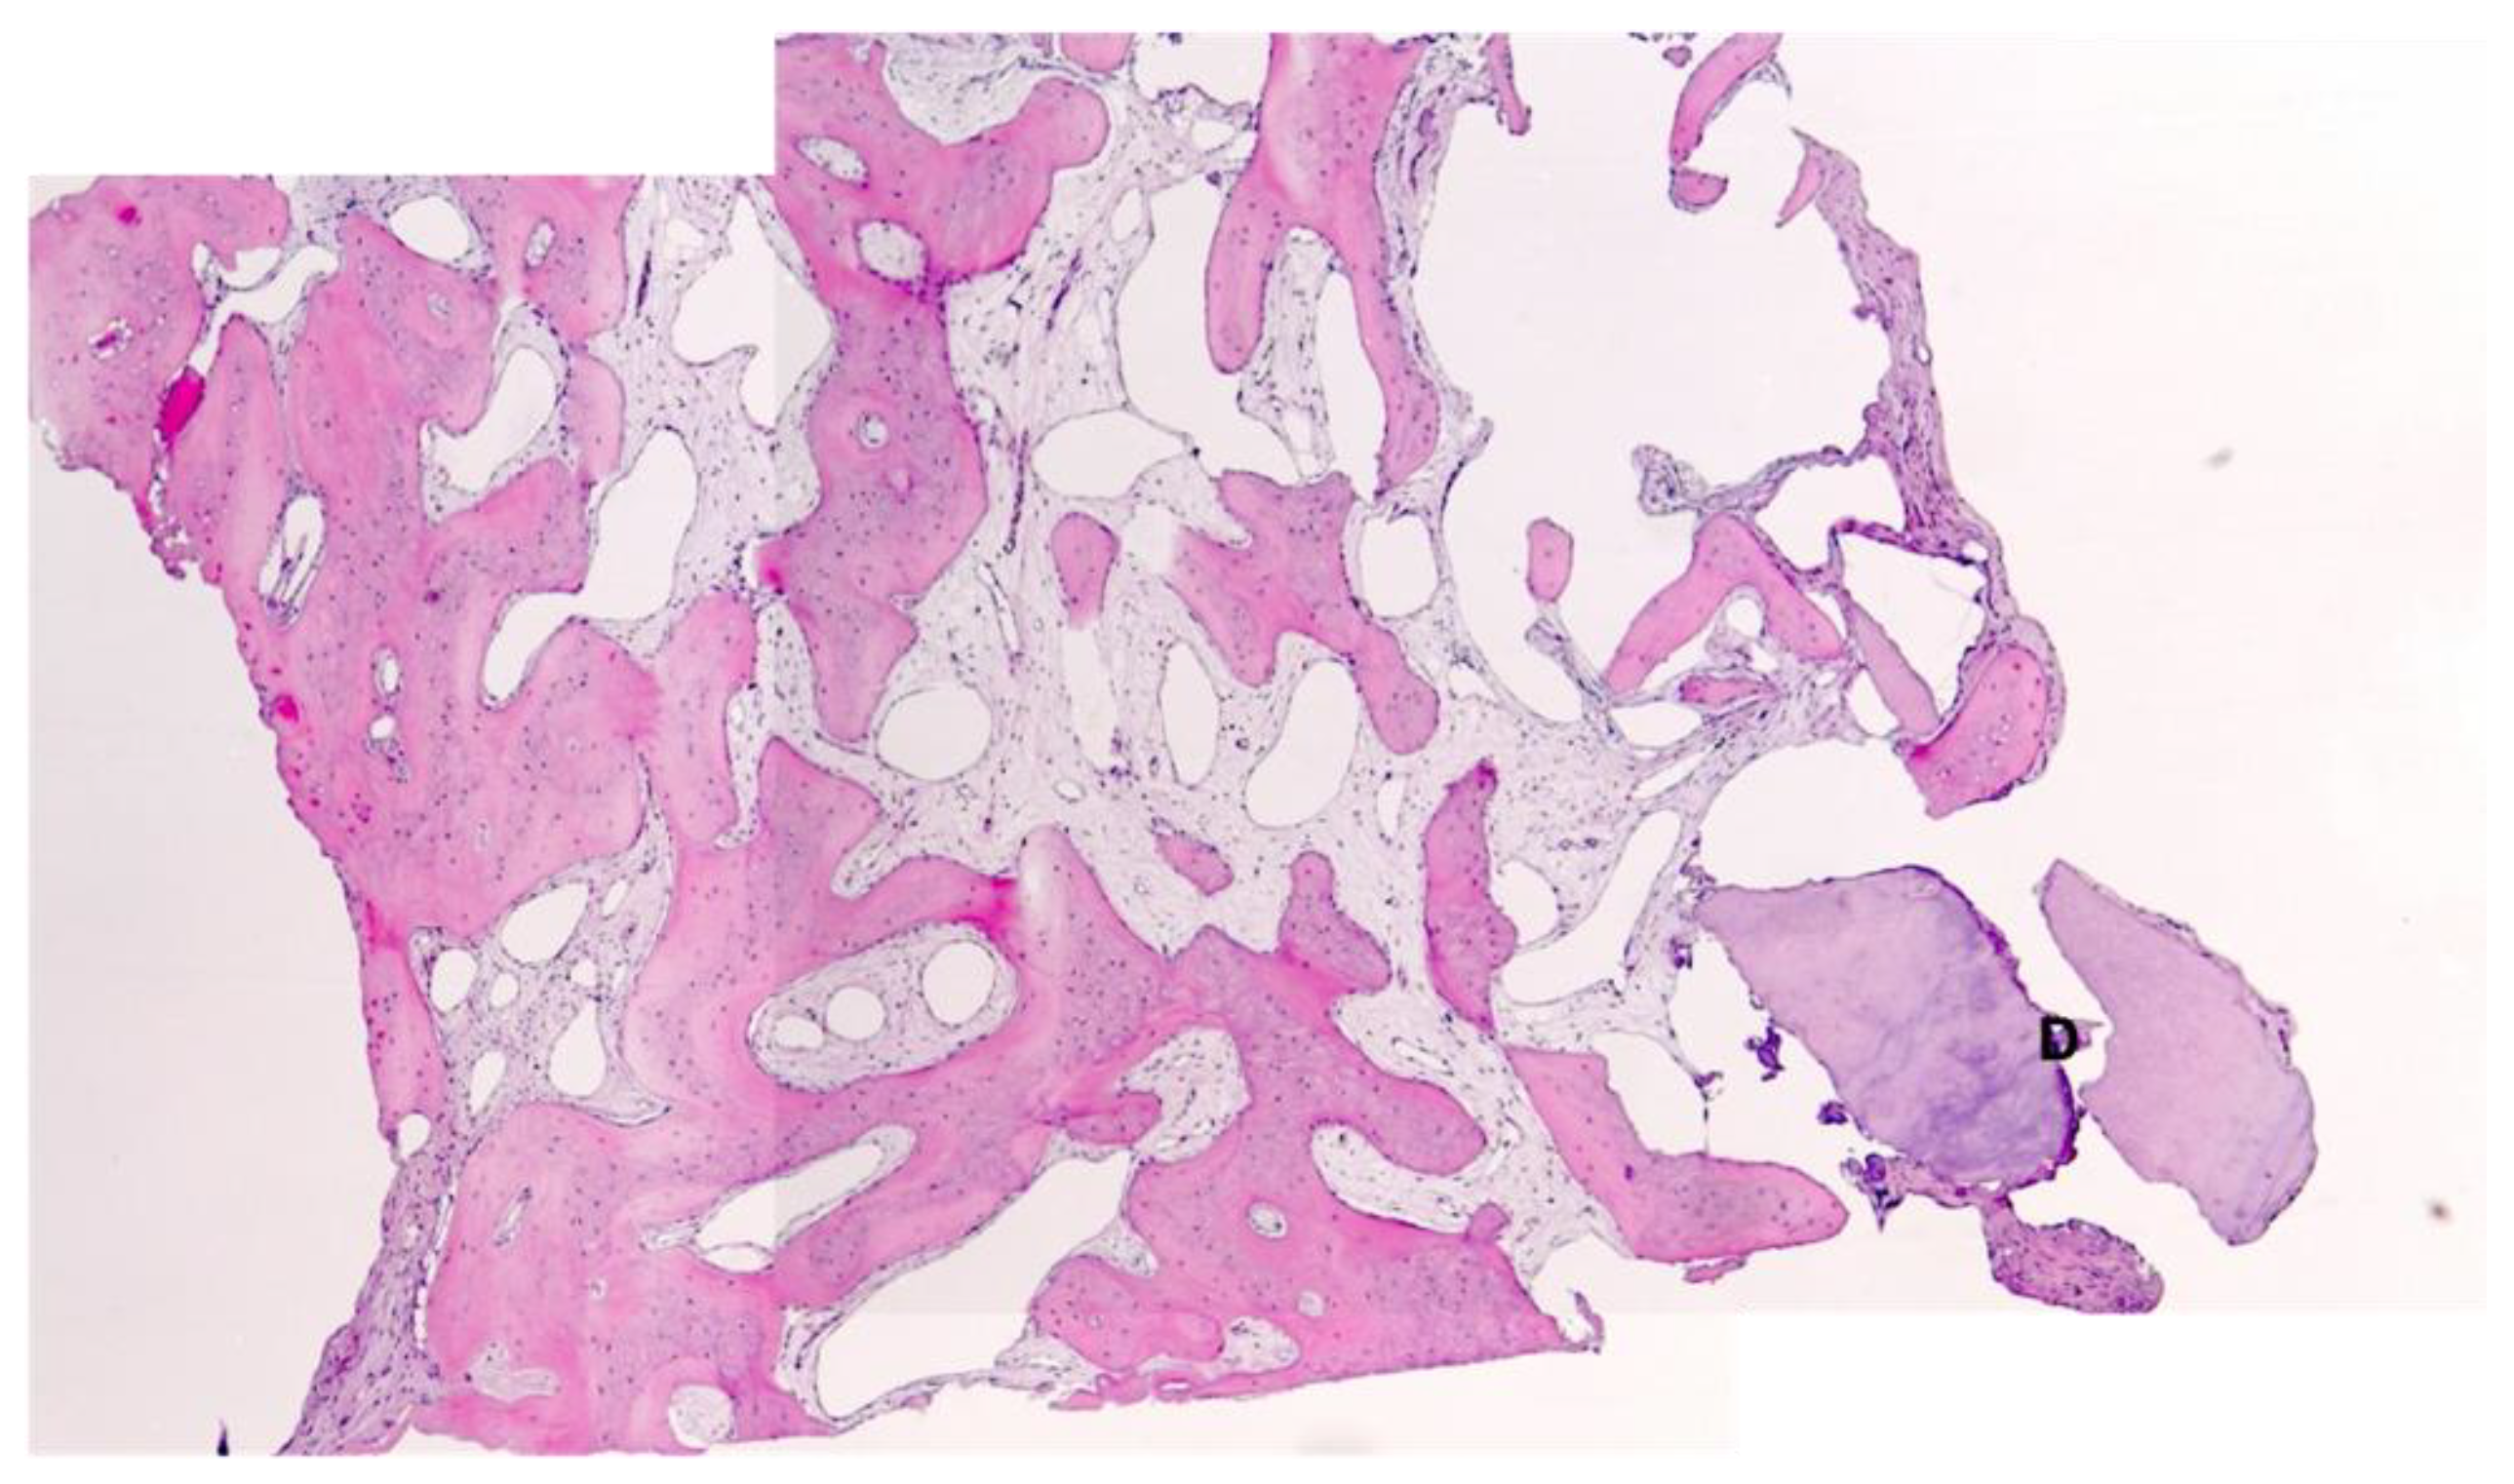

Histological Analysis

3. Results

3.1. Bone Quality